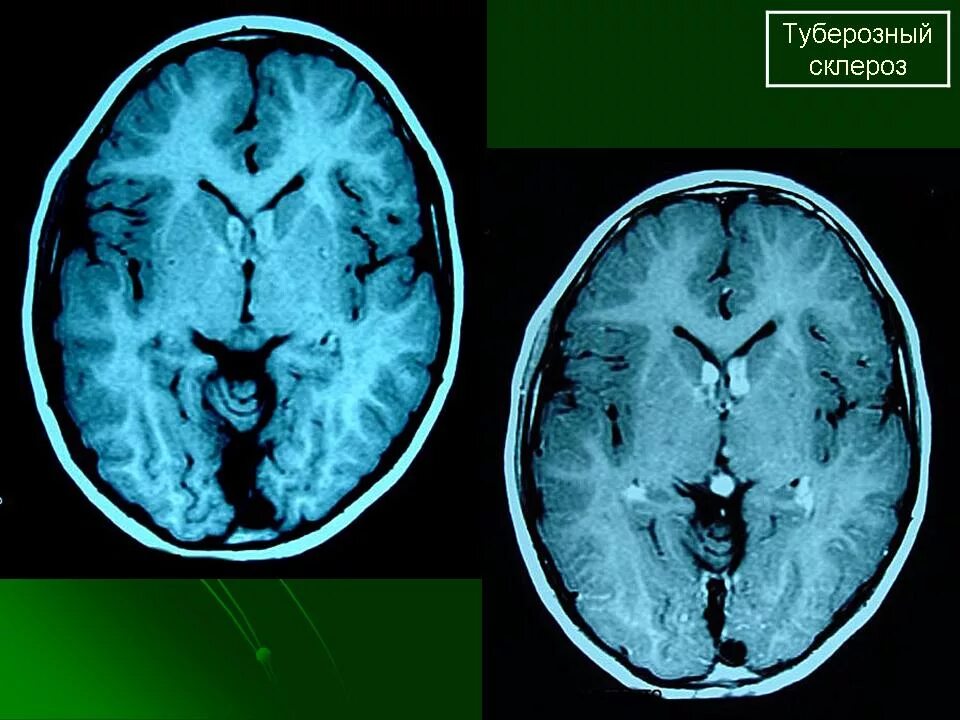

Туберкулезный склероз